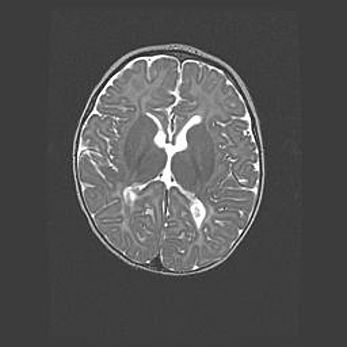

Мальформация Денди-Уокера. Киста задней черепной ямки.

Агенезия мозолистого тела.

Возраст: 2,5 месяца

Вес: 2420 г

Пол: женский

Окружность головы: 37 см

Срок гестации: 32 недели

Мальформация Денди—Уокера — редкий вид патологии ЦНС, представляющий собой врожденный порок развития каудального отдела ствола и червя мозжечка, ведущий к неполному раскрытию срединной (Мажанди) и латеральных (Лушка) апертур IV желудочка мозга. Для этогно синдрома характерна триада симптомов: гипотрофия червя мозжечка и/или полушарий мозжечка, кисты задней черепной ямки, гидроцефалия различной степени. В 70% случаев порок сочетается и с другими аномалиями головного мозга, в частности с агенезией мозолистого тела.